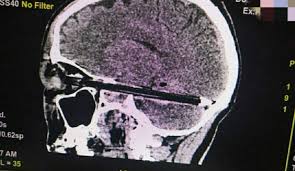

سجلت منطقة روستوف في روسيا حادث غريب لاستقرار قلم في جمجمة رجل دون سبب معروف.

كما وذكر الأطباء أن القلم دخل في جمجمة الرجل حتى وصلت إلى نهاية مؤخرة الجمجمة من خلال عينه.

كما وأضاف الأطباء أن الوقت لم يسعفهم لسؤال المريض عن سبب وجود القلم في جمجمته. لكنهم نجحوا في استخراج القلم من رأسه.